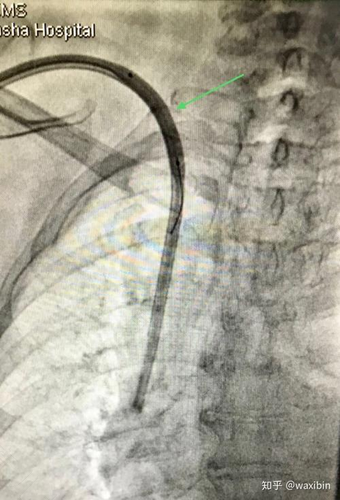

造影剂一般三天就可以排出体外了,它是不会被人体吸收的。一般情况下,做办理卵管造影手术时注射的造影剂量也是很少的,并且在做好造影检查后造影液可以通过输卵管的蠕动来排出体外。而且通过造影不但可以检查出输卵管是否通畅,而且还可以看出输卵管的具体堵塞部位,此方法非常的安全,而且没有明显的痛苦,是检查不孕不孕的一项非常常规项目。